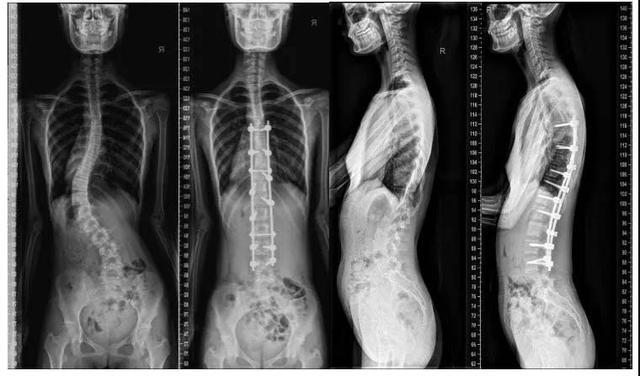

驼背矫正手术多少钱(治疗脊柱侧弯花费近13万) - 上海资讯网

患强直性脊柱炎男子驼背畸形手术后弯了17年的腰直了